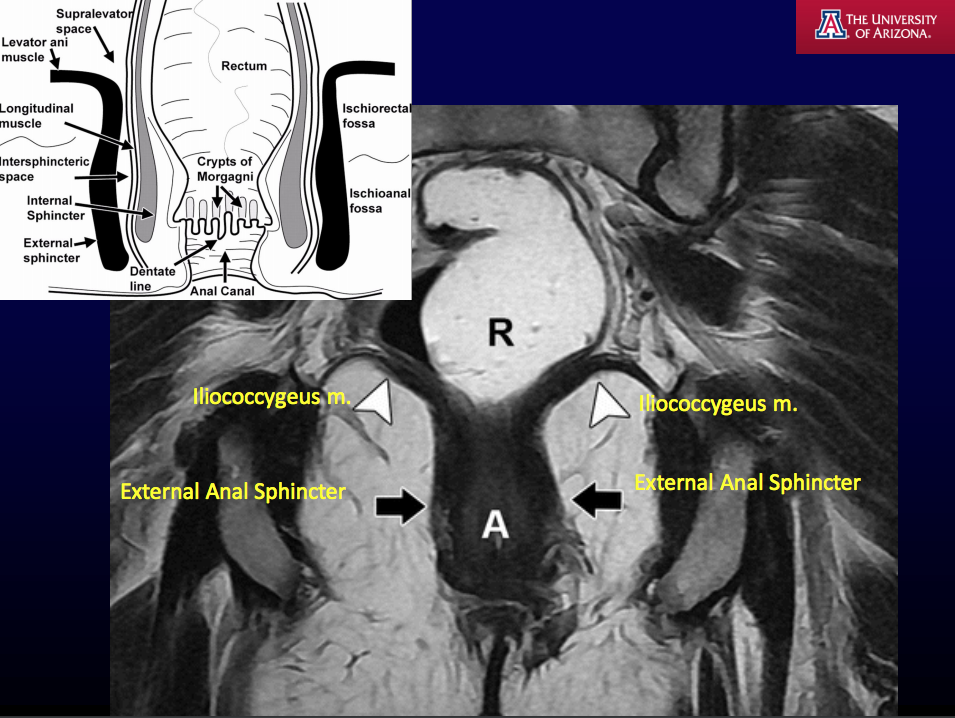

MRI T2WI fat is [] and fluid is [].

MRI T2WI fat is bright and fluid is bright.